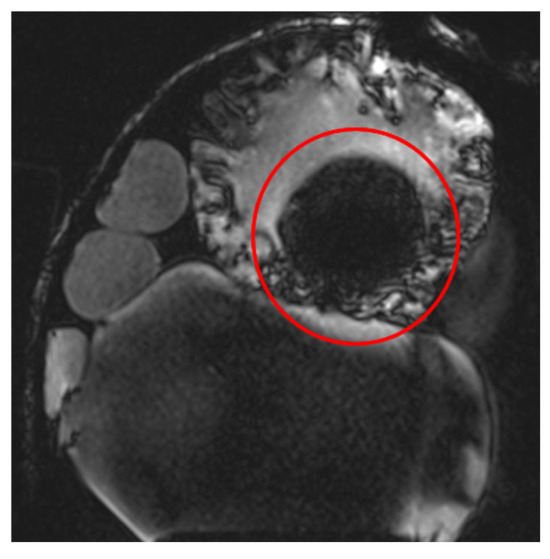

The Turbo Spin Echo (TSE) sequence was extensively utilized in this study due to its reduced sensitivity to susceptibility artifacts. This sequence is applicable to multiple contrast types (T1, T2, and Proton Density (PD)) and features an Echo Train Length (ETL) parameter, which controls sequence acceleration. Higher ETL values improve local image homogeneity but can also degrade spatial resolution. At extremely high ETL values (e.g., ETL = 45), a noticeable reduction in image quality is observed, as seen in Figure 6 (t2_tse_fs_tra sequence). Longer ETL values (tens of echoes) result in a blurred spatial resolution, which affects the quality of T2-weighted images.

Figure 6.

Images demonstrating the impact of varying Echo Train Length (ETL) values in the TSE sequence. Higher ETL values improve local image homogeneity but lead to a reduction in spatial resolution, with extreme ETL values (e.g., ETL = 45) causing noticeable image blurring, as observed in the t2_tse_fs_tra sequence.